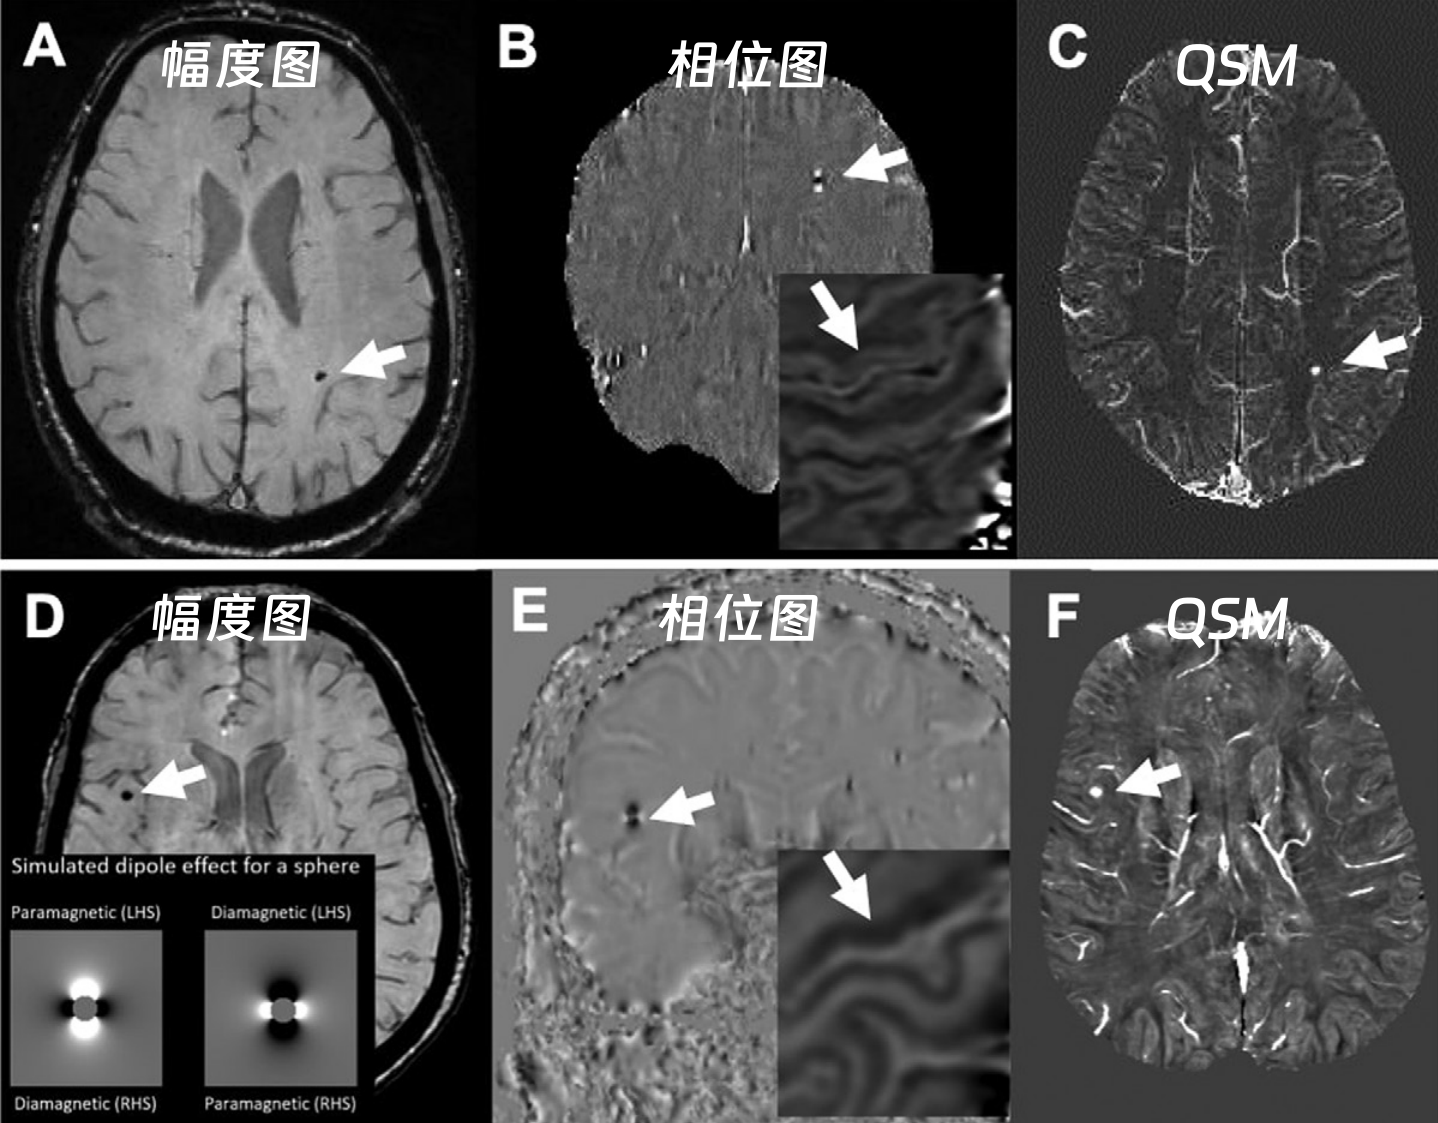

临床使用的SWI图像包含相位图像(Phase Imaging)和幅度图像,两者既可单独分析,也可经后处理融合,生成可视化效果更佳的SWI图像,从而实现对微小静脉结构、出血灶及代谢产物的精准显示。

在SWI图像判断时,西门子设备上钙化在相位图呈低信号,而GE、飞利浦上呈高信号,这是因为不同厂商采用的相位坐标系统不同

不同厂商磁共振设备的SWI相位图信号差异,源于相位坐标系的左右手系统区别:

01

右手坐标系(飞利浦、GE)

坐标特性:顺磁性物质产生负相移,相移越大相位图越亮(灰度越高)。

信号表现:

出血(顺磁性):相位图呈低信号,幅度图及 MIP 图呈低信号。

钙化(抗磁性):相位图呈高信号,幅度图及 MIP 图呈低信号。

物质判断:

若幅度图 / MIP 图为低信号,且相位图为高信号→ 抗磁性物质(如钙化)。

若幅度图 / MIP 图为低信号,且相位图为低信号→ 顺磁性物质(如铁沉积、钆沉积、出血)。

02

左手坐标系(西门子、佳能)

坐标特性:顺磁性物质产生正相移,相移越大相位图越亮(灰度越高)。

出血(顺磁性):相位图呈高信号,幅度图及 MIP 图呈低信号。

钙化(抗磁性):相位图呈低信号,幅度图及 MIP 图呈低信号。

若幅度图 / MIP 图为低信号,且相位图为高信号→ 顺磁性物质(如铁沉积、钆沉积、出血)。

若幅度图 / MIP 图为低信号,且相位图为低信号→ 抗磁性物质(如钙化)。

49b3dd764ccd67d6c06a2d54253d9177.png

西门子与GE机器—出血图像对比

(QSM:定量磁化率成像)